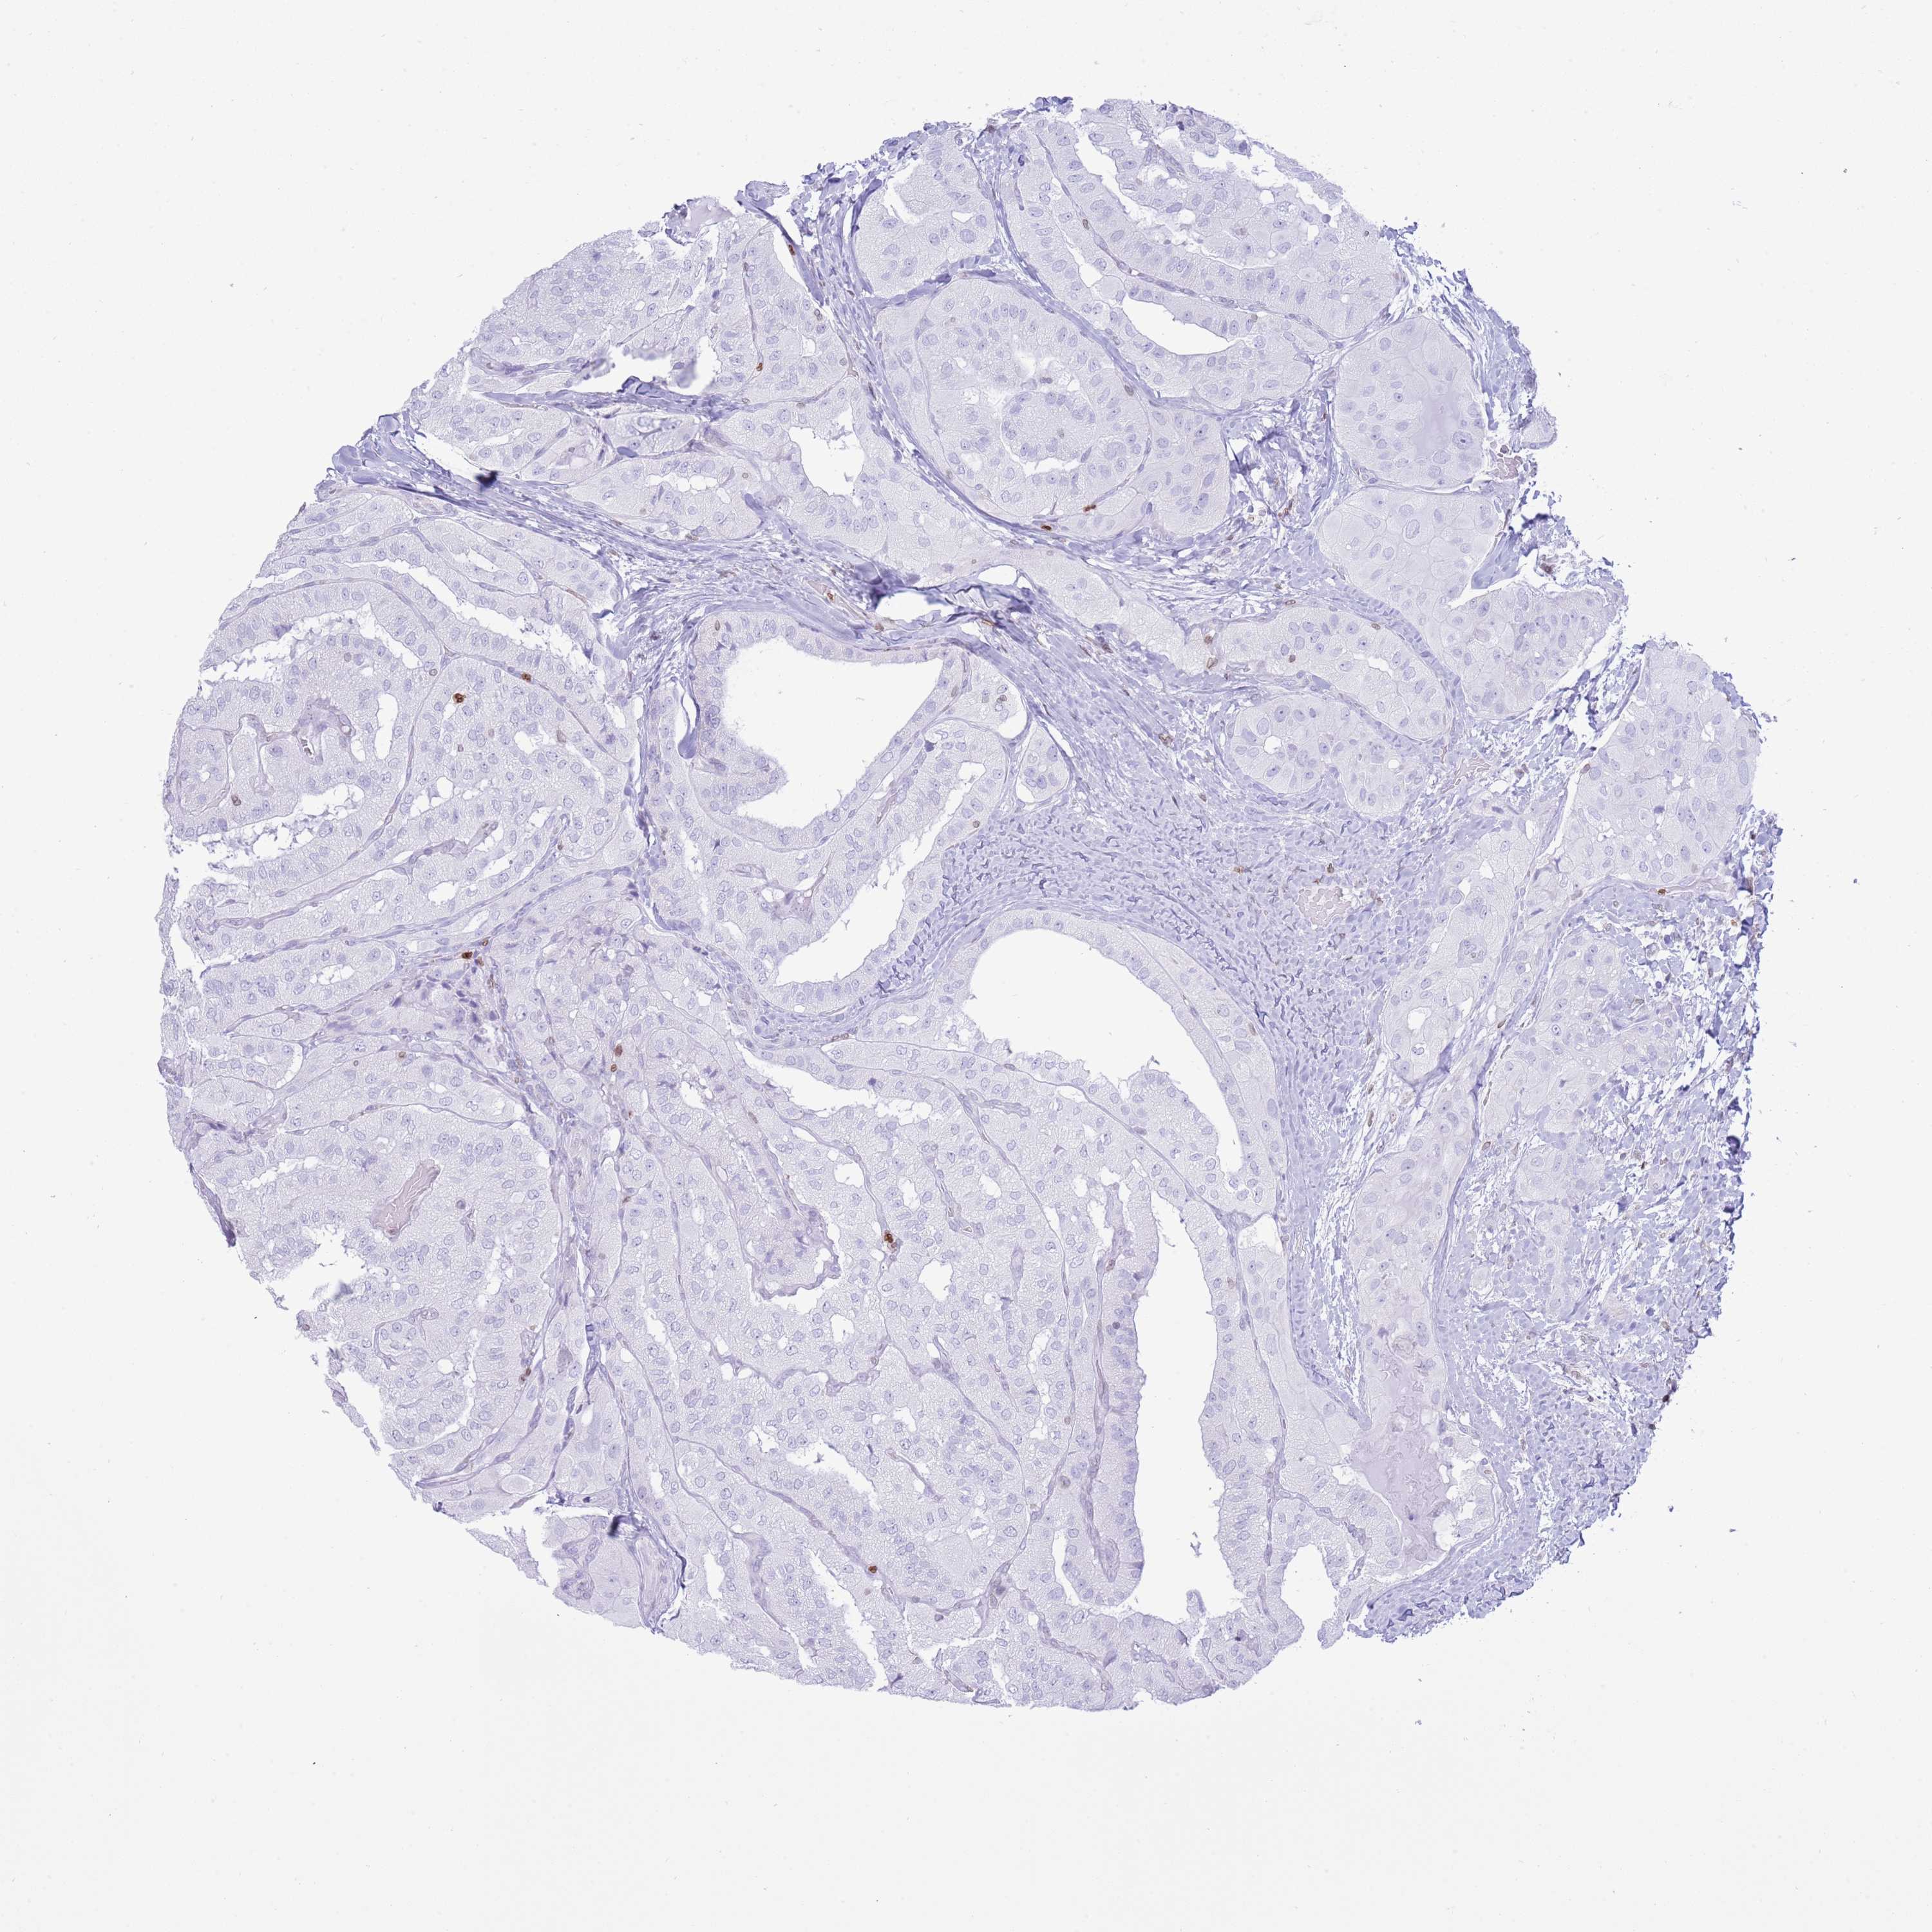

THYROID CANCER - Protein expressioni

A mouse-over function shows sample information and annotation data. Click on an image to view it in a full screen mode. Samples can be filtered based on level of antibody staining by selecting one or several of the following categories: high, medium, low and not detected. The assay and annotation is described here.

Note that samples used for immunohistochemistry by the Human Protein Atlas do not correspond to samples in the TCGA dataset.

Antibody stainingi

Antibody staining in the annotated cell types in the current human tissue is reported as not detected, low, medium, or high, based on conventional immunohistochemistry profiling in selected tissues. This score is based on the combination of the staining intensity and fraction of stained cells.

Each image is clickable and will lead to virtual microscopy that enables deeper exploration of all samples and also displays staining intensity scores, fraction scores and subcellular localization as well as patient and tissue information for each sample.

Antibody HPA049840

Antibody HPA062236

Staining

High

Medium

Low

Not detected

Intensity

Strong

Moderate

Weak

Negative

Quantity

>75%

75%-25%

<25%

None

Location

Nuclear

Cytoplasmic/membranous

Cytoplasmic/membranous,nuclear

Papillary adenocarcinoma, NOS

Follicular adenoma carcinoma, NOS